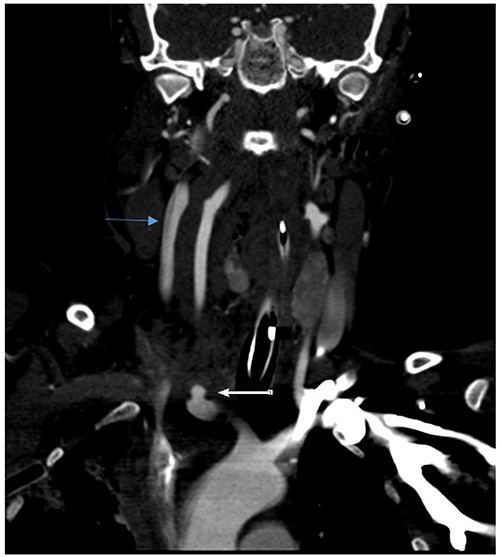

She remained hemodynamically stable; therefore, the patient was transferred to Computed tomography (CT) scan for optimal preoperative planning. Head and neck CT showed right common carotid dissection with a small pseudoaneurysm (Fig. 2). And bullet fragment causing proximal filling defect measuring 1.4 cm long without active extravasation. Surrounding the right common carotid was a hematoma extending to the anterior neck and superior mediastinum. Also, Right subclavian dissection with three pseudoaneurysms (Fig. 3) proximal and distal to the right vertebral artery takeoff, the largest measures 1.1 × 0.8 cm. Multiple scattered metallic fragments were also noted at the subcutaneous tissue of bilateral temporal bones and the occipital area.

Right common carotid intimal flap (upper arrow) and pseudoaneurysm at origin (lower arrow).